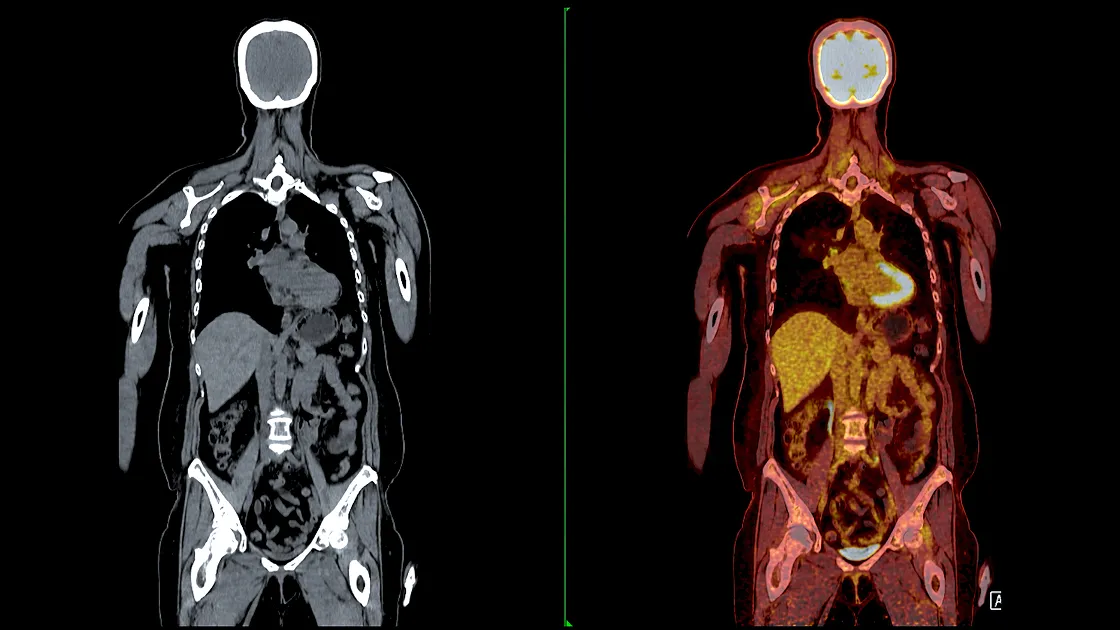

• PET検査:全身がん検査

検査毎に検出が苦手ながんの種類やカバーできない部位がある

また、PET/CTやMRIは一般に腫瘍が1cm程度の大きさにならないと発見できない

PET/CTやMRIには、検出が苦手ながんの種類や、カバーできない部位があります。また、一般に腫瘍が1cm程度の大きさにならないと発見できません。その点、マイクロCTC検査は全身のがんリスクを一度の検査で確認でき、腫瘍が1cm以内の大きさでも検出することが可能です。